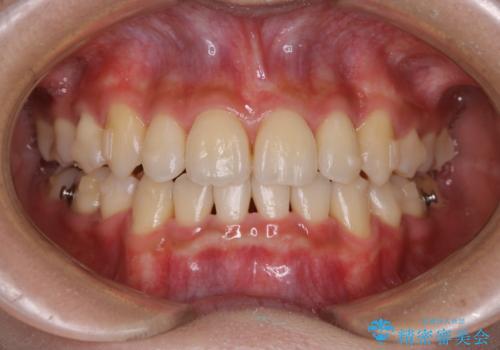

- 元々は海外でワイヤー矯正を行っていたが、コロナ禍で海外への往来が難しくなり、治療を中断せざるを得なくなってしまった方です。

ご本人のご希望により、インビザラインによる治療を行いました。

ブラケット除去直後に目立っていた下顎前歯部の大きなブラックトライアングルもあまり目立たなくなり、大変喜んでいただけました。